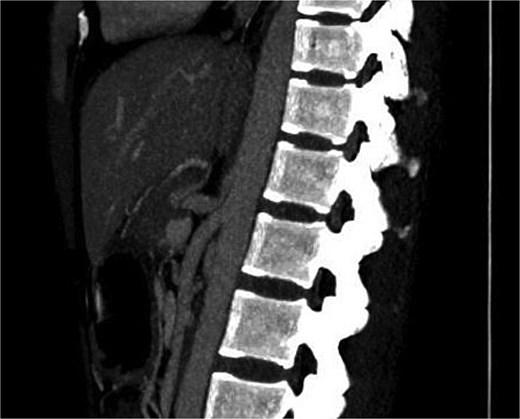

Initial scanning with abdominal ultrasound was inconclusive. Subsequently contrast-enhanced computed tomography (CECT) of the abdomen was done, which showed a marked focal narrowing at the origin of celiac trunk superior aspect by the arcuate ligament followed by post stenotic dilatation. No evidence of atherosclerosis seen (Fig. 1).

Showing marked focal narrowing at the origin of celiac trunk superior aspect by the arcuate ligament followed by post stenotic dilatation.